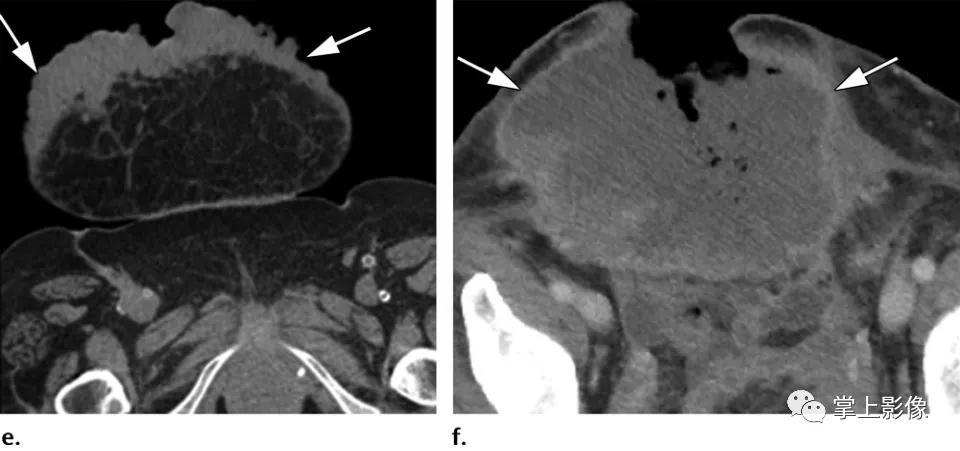

35岁女性腹壁硬纤维样瘤,经皮穿刺活检证实。(A)轴位CT显示以左直肌鞘为中心的高强化腹壁肿块(箭头)。(b-d)轴位平扫T1WI显示低信号肿块。注射钆对比剂后,在动脉期(C)、门静脉期(未显示)和延迟期(D)图像上可见肿块(b-d箭头)渐进性均匀强化。(E)超声图像显示低血流低回声肿块(箭头)